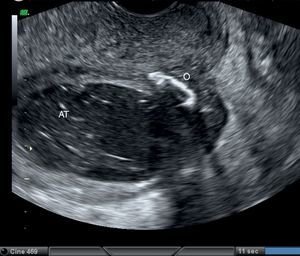

En la exploración, se encontraba normotensa, afebril, con palidez mucocutánea. Presentaba importante distensión abdominal y peritonismo generalizado. La exploración ginecológica fue normal. Las pruebas de laboratorio revelaron leucocitosis con neutrofilia del 87% y anemia leve con bioquímica, coagulación y sedimento de orina normales. En la ecografía transvaginal (fig. 1) únicamente destacaba una imagen quística en fosa ilíaca derecha de 86×45mm, de trabeculado fino, sin tabiques ni papilas, con una calcificación en su polo craneal, indicativa de quiste dermoide. La TC abdominopélvica (figs. 2 y 3) mostró una lesión quística lobulada de dimensiones superponibles, de probable dependencia anexial derecha con contenido líquido, pared gruesa, lisa y bien delimitada, con una calcificación milimétrica en su interior, marcada dilatación de asas intestinales sin presencia de tránsito, indicativa de íleo adinámico y una pequeña cantidad de líquido libre entre asas y adyacente al fundus uterino.